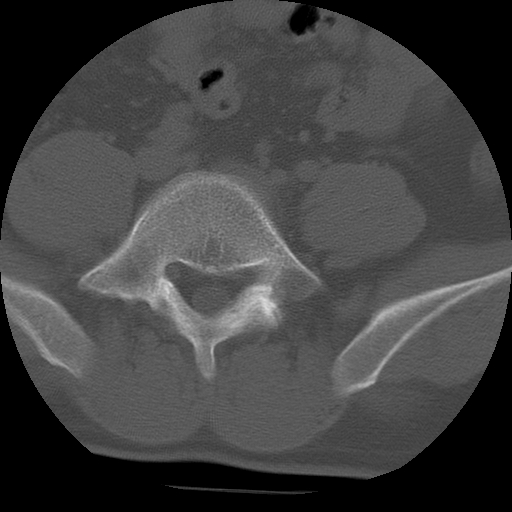

标题: CT24390:男,23岁,腰痛就诊。

男,23岁,腰痛就诊。

腰5右侧横突肥大伴假关节形成.

支持!图像少,再往下扫骶髂关节面,椎小关节毛糙,青年男性需排除as,实验室查b27。

腰5右侧横突肥大伴假关节形成

腰5右侧横突肥大伴假关节形成!支持!

l5右侧横突肥大伴假关节形成。

腰椎骶化或骶椎腰化常见。